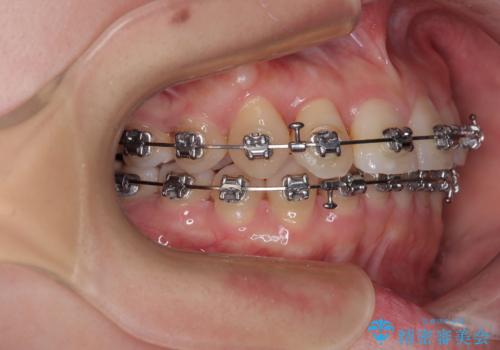

捻転の強い前歯 ワイヤー装置での非抜歯矯正

- 矯正装置

- メタルブラケット

- 前歯のデコボコ、特に90度捻れている上顎前歯を気にして来院された患者様です。

マウスピースでもワイヤーでも対応可能でしたら、捻転が非常に強いことから、患者様と相談の上ワイヤー装置にて矯正治療を行うこととしました。

捻転を解消する際に、歯列全体が前方に突出して出っ歯の仕上がりとなることが懸念されたため、補助装置を用いて上顎歯列全体を後方に移動する力をかけることとしました。